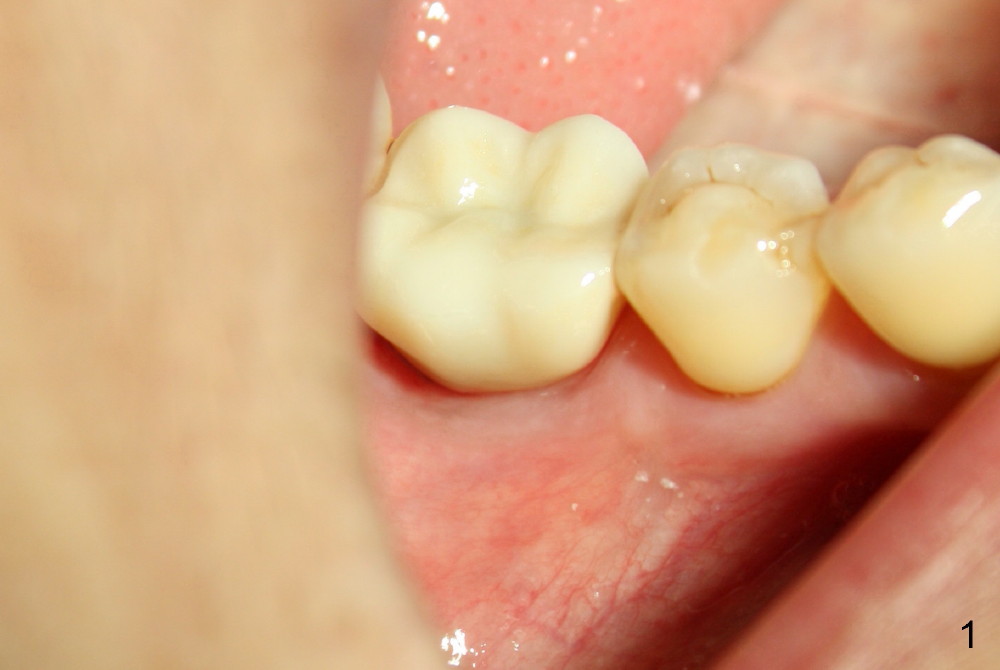

Thirteen months post bone graft via buccal approach, the patient has remained asymptomatic. There is no sign of infection buccally (Fig.1), but the lingual gingiva is erythematous (Fig.2 arrowheads) with deep pocket (Fig.3). Since the patient will be out of country for 7 months, exploration is going to be done immediately. Preop PA reveals mesial bone loss (Fig.4 M).

There is no symptom or sign of periimplantitis 3 years 8 months post 2nd bone graft (Fig.7-10). However, the patient complains of gingival hemorrhage 8 months later (Fig.11,12 (buccal), 13 (lingual view)). Water Pik is recommended.